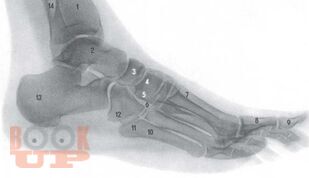

Монография посвящена хирургическому лечению гнойно-некротических поражений стопы при сахарном диабете. В работе отражен современный взгляд на патогенез, классификацию, клинику, диагностику и дифференциальную диагностику синдрома диабетической стопы. Представлены диагностические и лечебные алгоритмы при гнойно-некротических поражениях стопы для догоспитального и стационарного этапов. Большая часть работы посвящена хирургической тактике и технике наиболее часто производимых хирургических вмешательств на нижней конечности с определением показаний к той или иной операции. Подробно рассматриваются вопросы, касающиеся органосохраняющих вмешательств (локальных операций на стопе). Пособие предназначено практикующим врачам – хирургам, эндокринологам, ортопедам, протезистам поликлиник и стационаров, занимающихся лечением поражений стопы при сахарном диабете.